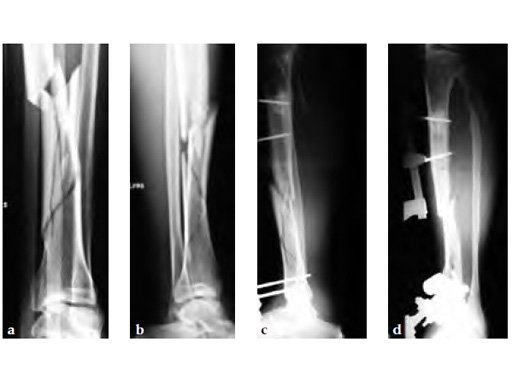

A 58-year-old male sustained a closed multifragmentary 42-C1 fracture in the distal tibia with compartment syndrome.

Case provided by Dankward Hntzsch, Tbingen, Germany

Primary treatment consisted of an external fixator and release of compartments.

Mobilization of the limb started with an applied external fixator.

Secondary treatment: insertion of an unreamed intramedullary nail with three ASLS screws inserted distally providing angular stability.

Partial weight bearing started on postoperative day 2 (with 2030kg). The weight was gradually increased over the following weeks. At 6 weeks, the patient was able to fully bear weight even though a high fibula fracture was present and no callus had yet formed. This suggests that angular stable interlocking of the nail markedly enhances stability. The patient was able to bear weight faster than planned and full weight bearing was possible with little pain.

Twelve-week follow-up shows callus formation, and the patient was able to fully bear weight without any pain.

The nail was removed 15 months postinjury as planned. There is good callus formation and proper healing of the tibia fracture.